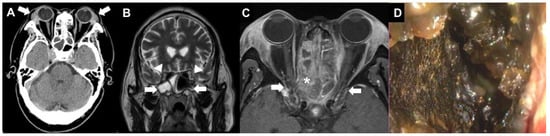

Acute Vision Loss as the Initial Manifestation of Granulomatosis with Polyangiitis Involving the Orbital Apex